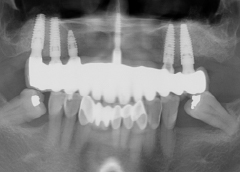

• Phương hướng điều trị:Cấy răng Implant toàn hàm trên (All On 6 ) và phục hình hàm sứ cố định.

• Trụ Implant sử dụng:Implant Mis C1 Đức và răng sứ Titan Mỹ.

• Răng sứ sử dụng:Phục hình răng sứ Titan Mỹ

• Cấy Implant All on 6 hàm trên trụ Implant Mis C1 Đức

• Phục hình răng sứ Titan Mỹ

Kết thúc quá trình trồng răng, cô Bạch Thúy đã có thể ăn uống thoải mái và tự tin hơn với nụ cười của mình. Cô cũng không quên gửi lời cảm ơn đến bác sĩ và đội ngũ nha khoa I-DENT đã luôn tận tâm và chu đáo.